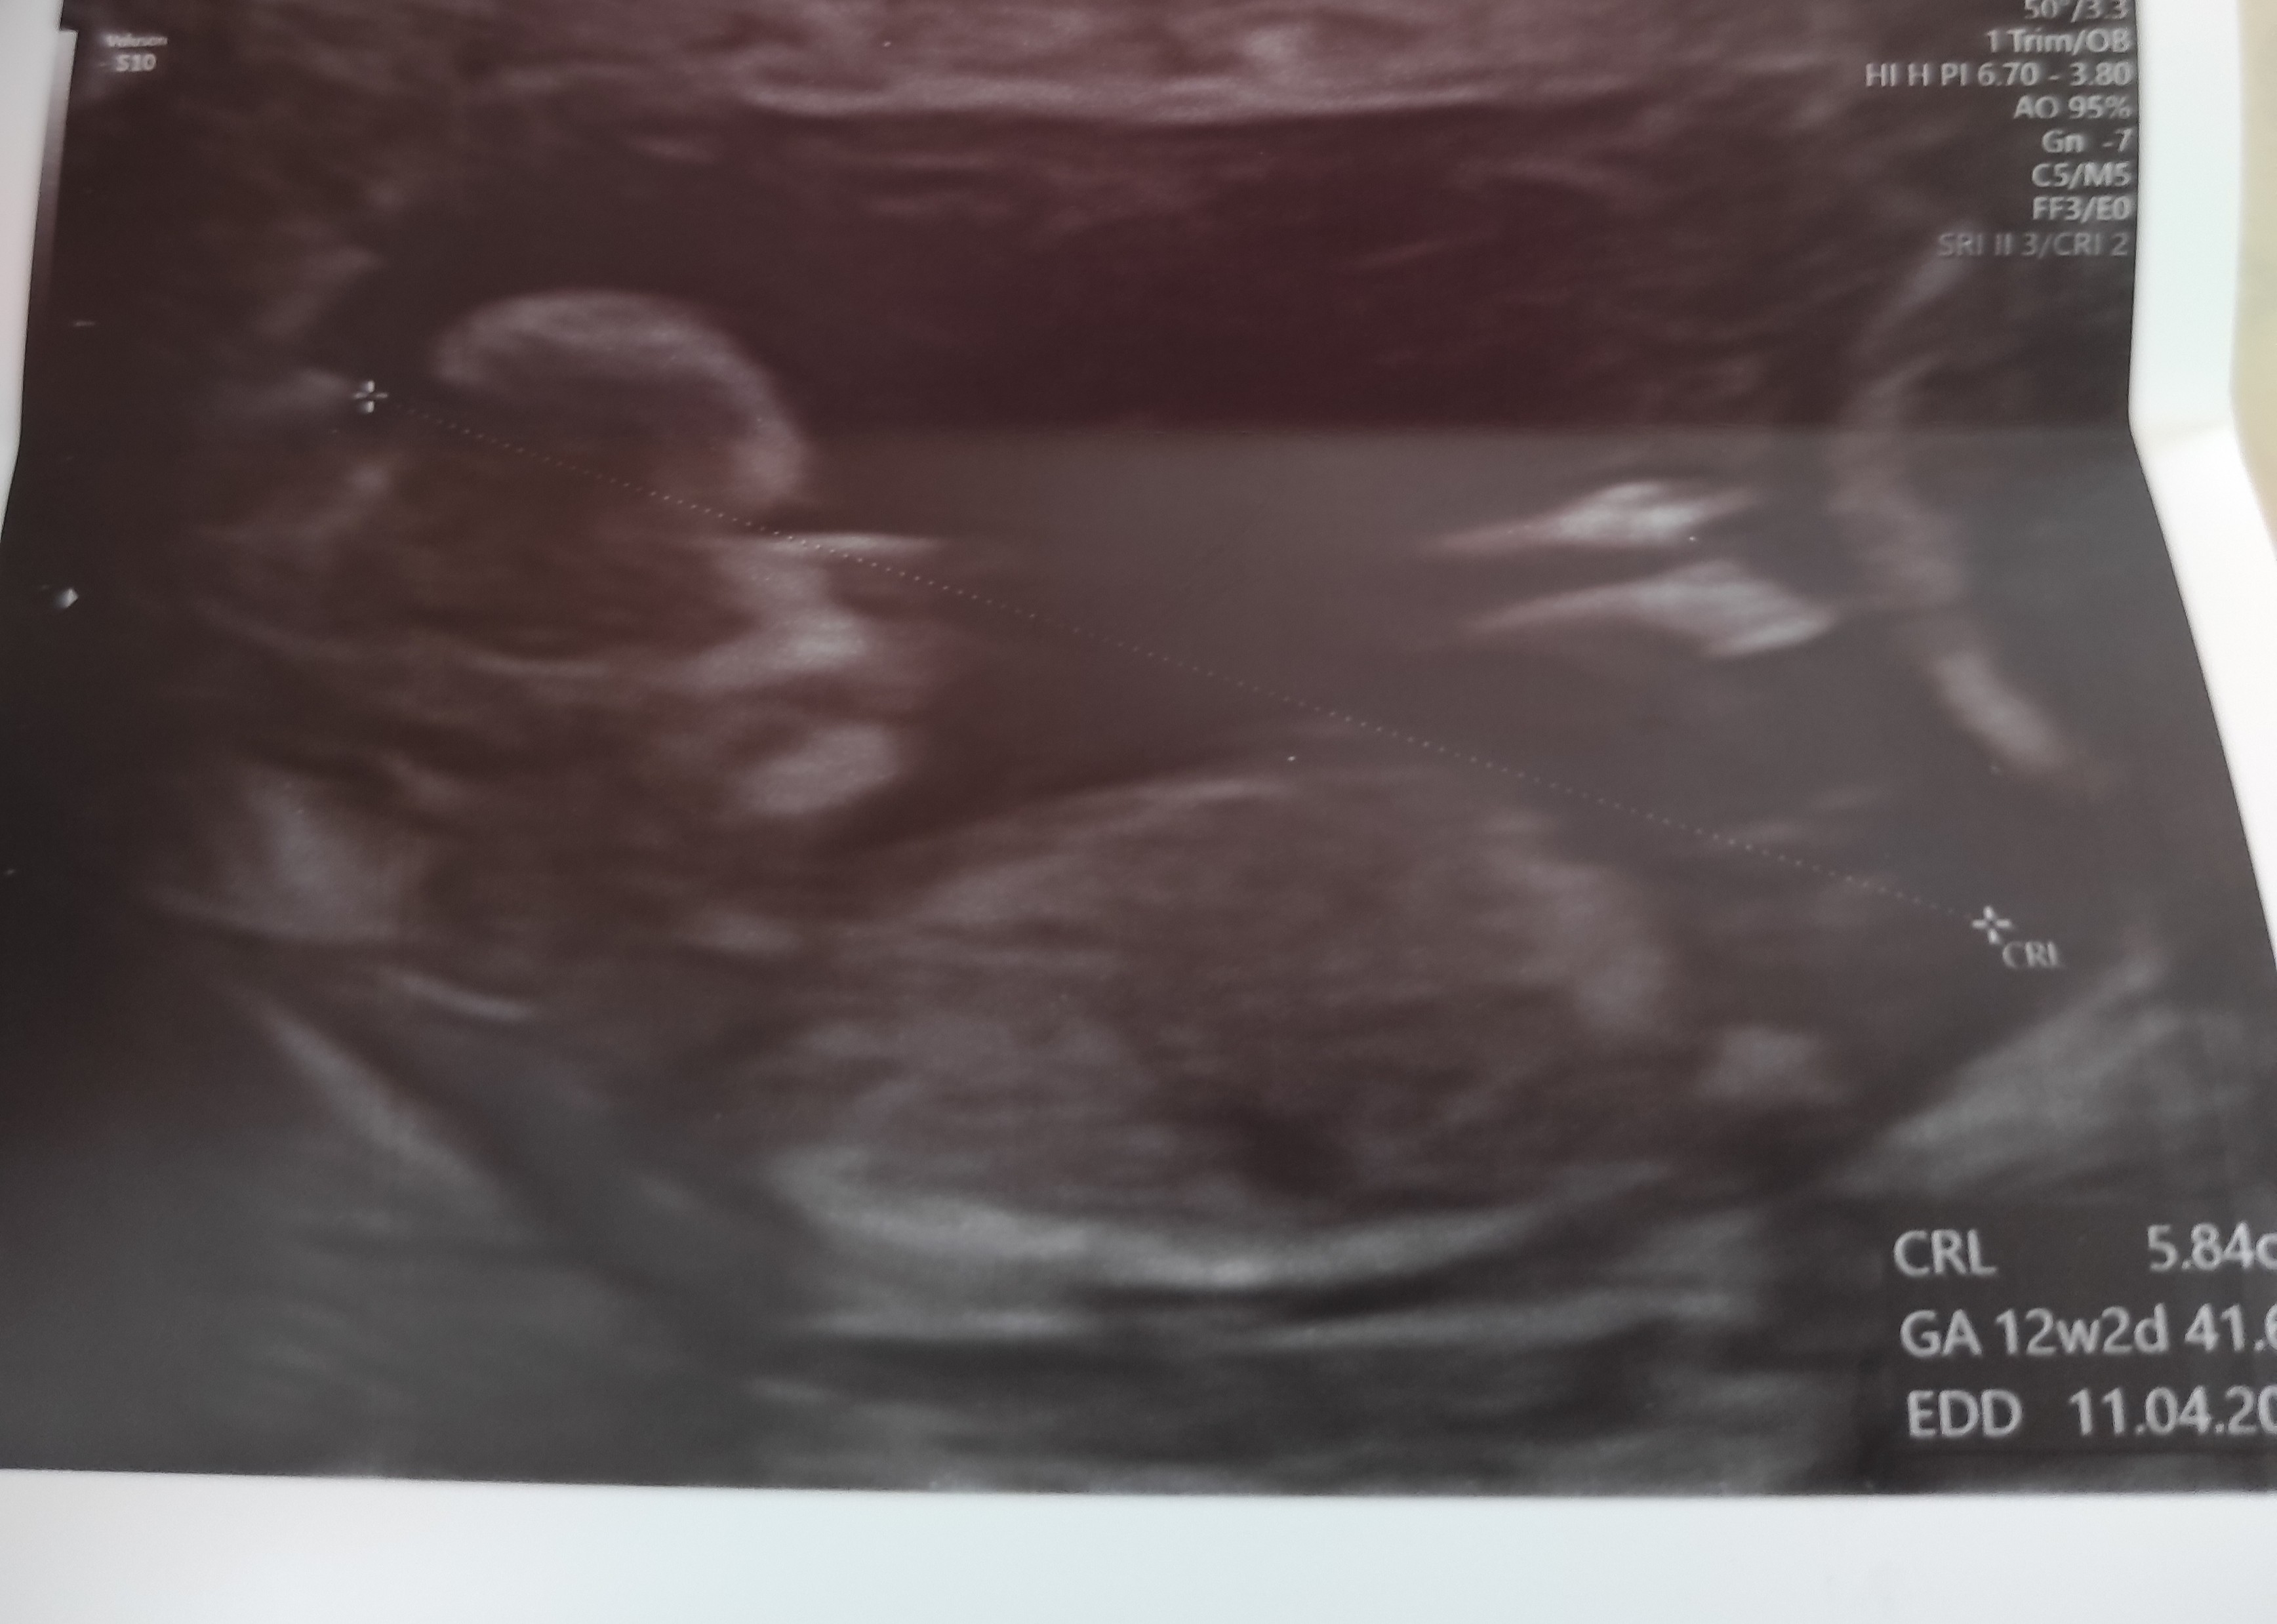

Dziewczyny, po prenatalnych wszystko jest dobrze 🥰🥰🥰🥰🥰 Tak bardzo, bardzo się cieszymy ♥️♥️♥️ Płci jeszcze nie poznaliśmy, ale najważniejsze, że Dzieciątko zdrowo się rozwija😊

Załączniki

• IMG_20210929_133524.jpg

IMG_20210929_133524.jpg

791 KB · Wyświetleń: 123